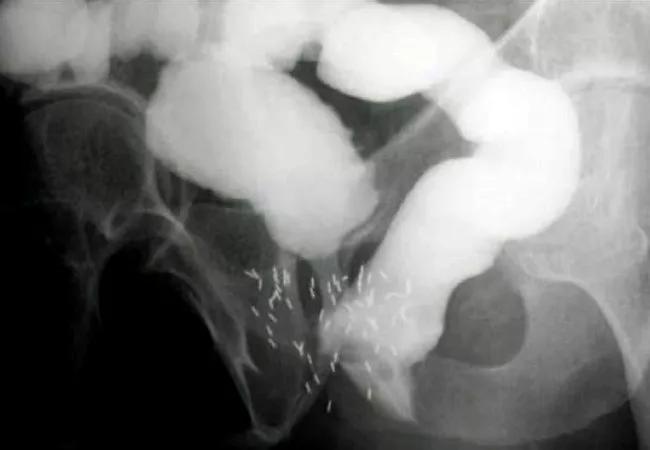

Contrast study demonstrating rectourethral fistula.

Contrast study demonstrating rectourethral fistula. Contrast outlines bladder and bowel, fistula between urethra and rectum, as well as brachytherapy seeds from prostate cancer treatment.